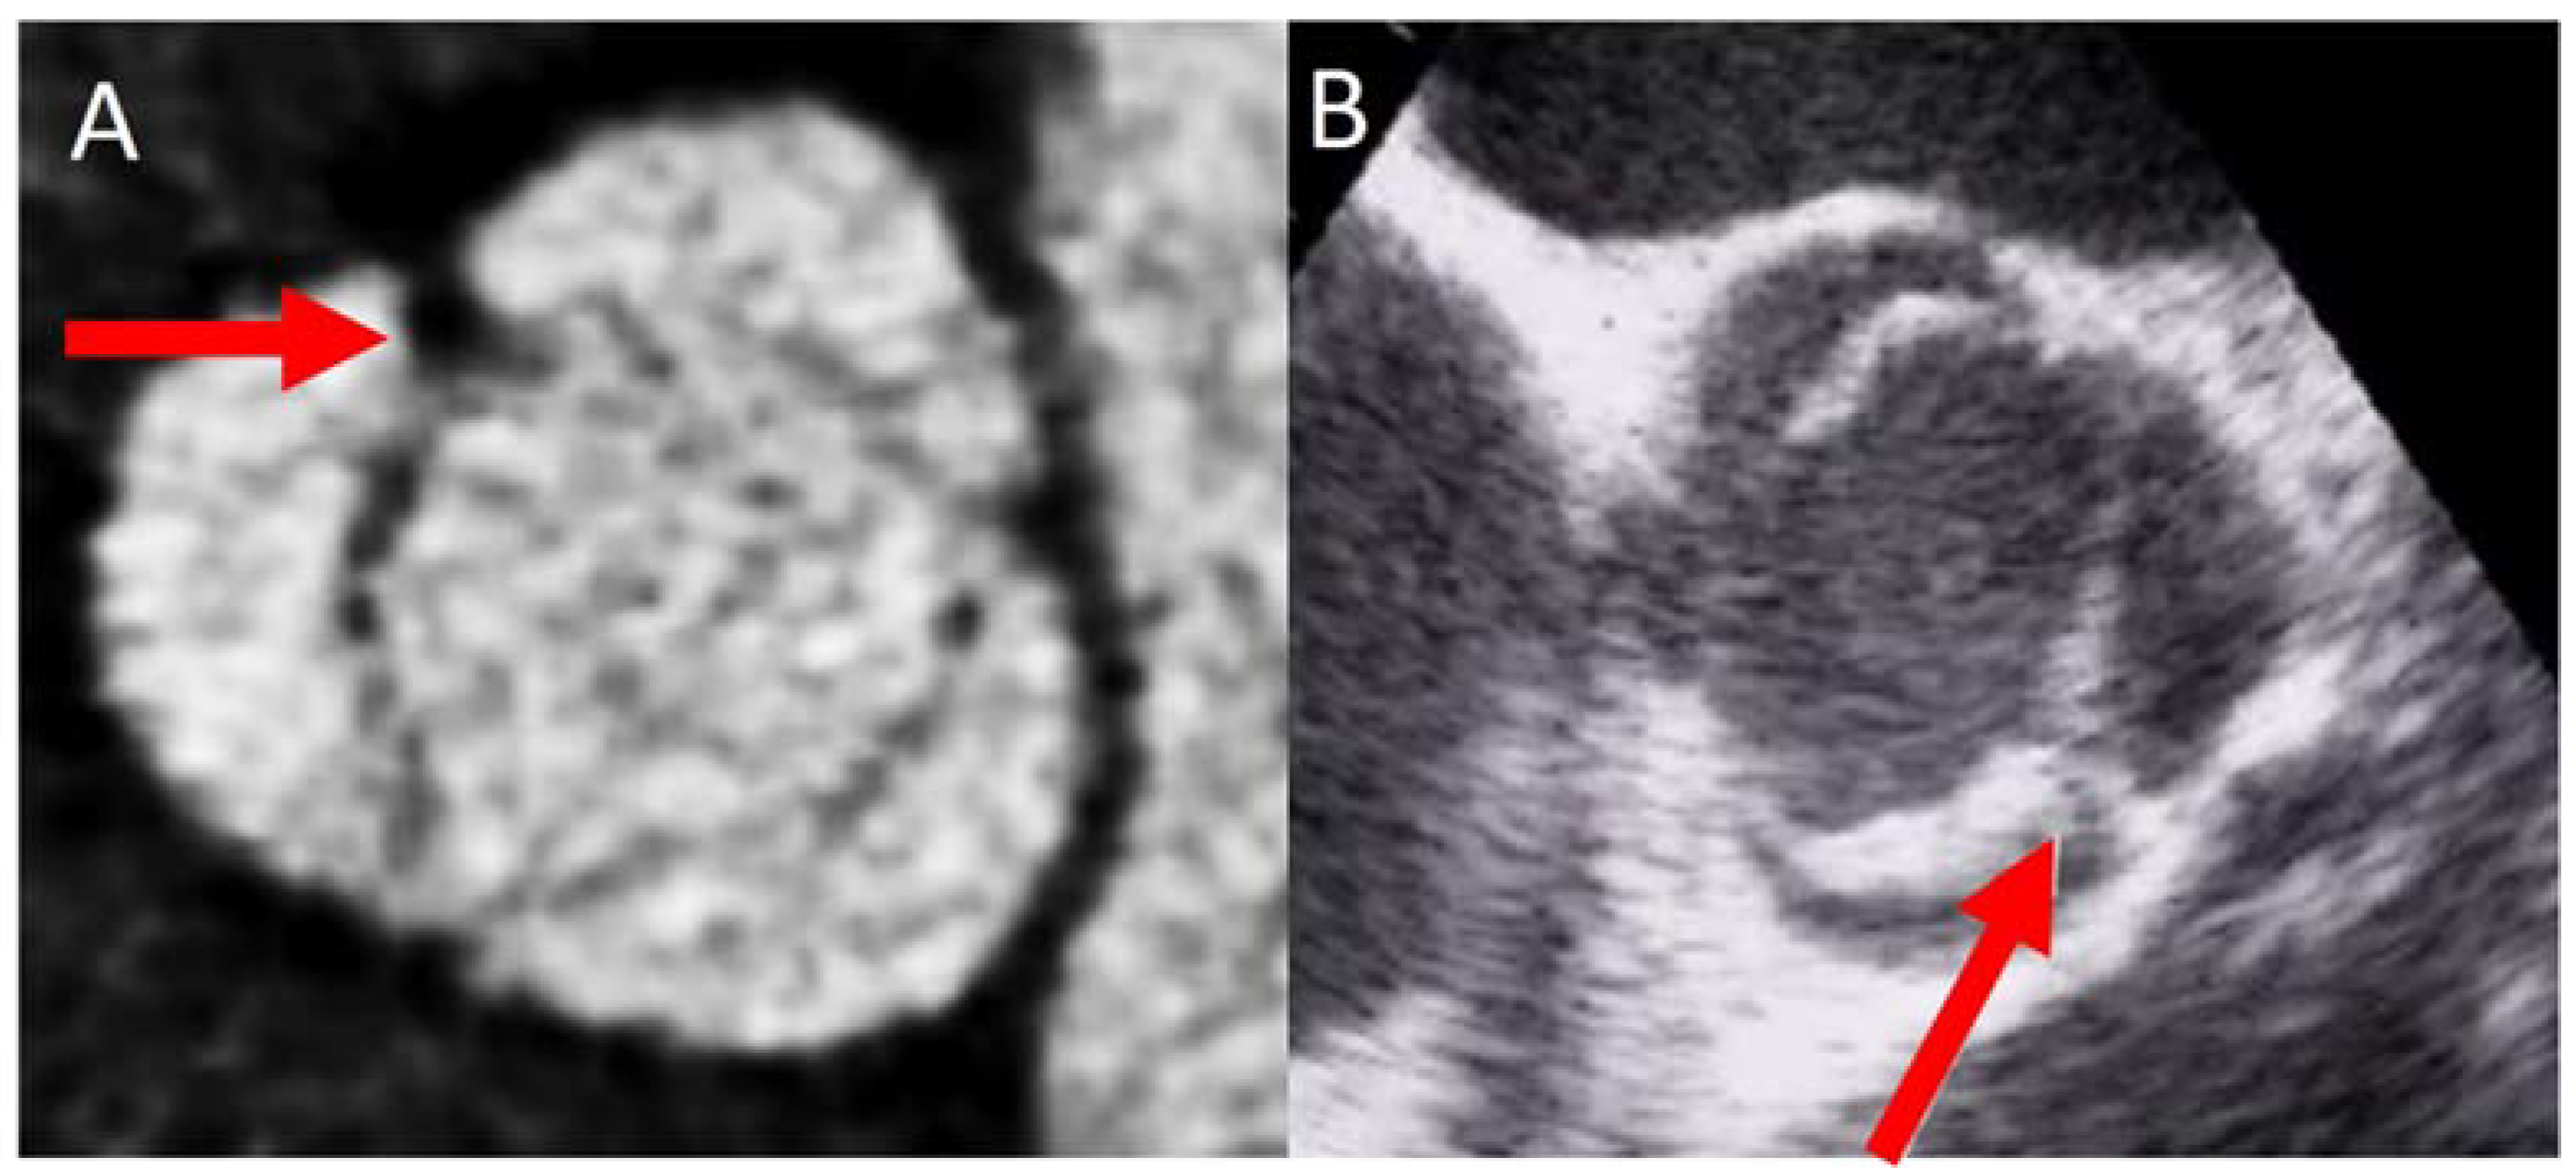

The most common type of BAV is the fused one (90–95% of the cases) [19]. This is described as two of the three cusps appearing fused within three aortic sinuses, resulting in two functional cusps commonly different in shape and size. A congenital fibrous ridge is often described between the fused cusps, and it is what we know as “raphe”. The most frequent BAV phenotype is the one with right−left (R−L) fusion, considered to be present in 75% of the cohort. This is followed by the right−non-coronary (R−N) fusion (20–25%), and finally the left−non (L−N) fusion (<3%). The two-sinus BAV type is uncommon and accounts for approximately 5–7% of cases. In contrast to the fused type, the two-sinus BAV appearance suggests that two roughly equal size-shape cusps, each cusp occupying 180 degrees of the annular circumference, are “formed” within only two aortic sinuses, resulting in a two-sinus/two-cusp valve [20] with a latero−lateral (side-to-side) or antero−posterior (front-and-back) position. The presence of an incomplete fusion of two leaflets (mini-raphe) cannot be easily visualized by TTE [21] (Figure 2). In these cases, we should use other techniques such as TEE and CT. This mini-raphe has been considered to be involved in aorta dilation [22].

Figure 2.

BAV with partial fusion (forma frustre). Arrows show the mini raphe by CT (A) and by TEE (B).